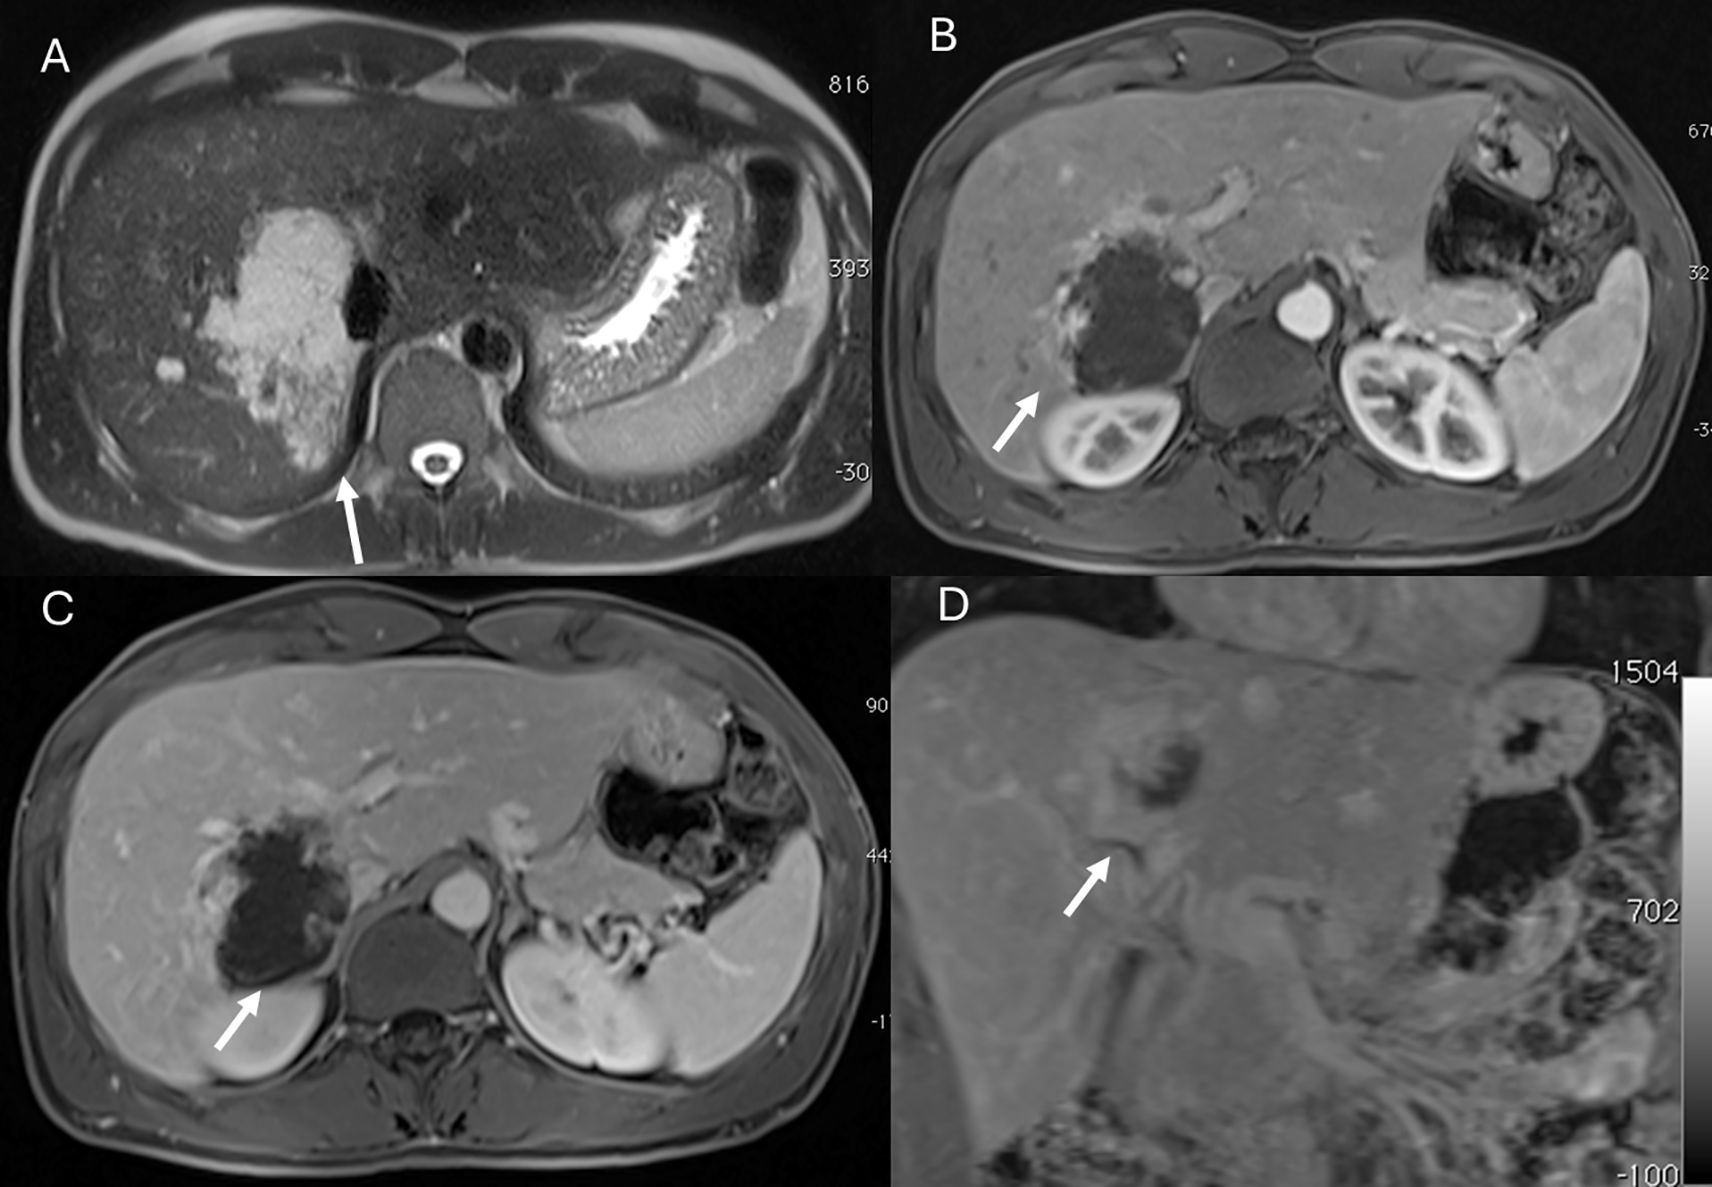

Figure 1. MRI assessment of liver hemangiomas (arrows). In (A) (T2-W sequence, axial plane), the hemangioma (arrow) shows hyperintense signal, and after non-specific contrast agent administration a progressive enhancement is seen (B) T1-W in axial plane during in arterial phase; (C) T1-W in axial plane during portal phase and (D) T1-W in coronal plane during late phase).